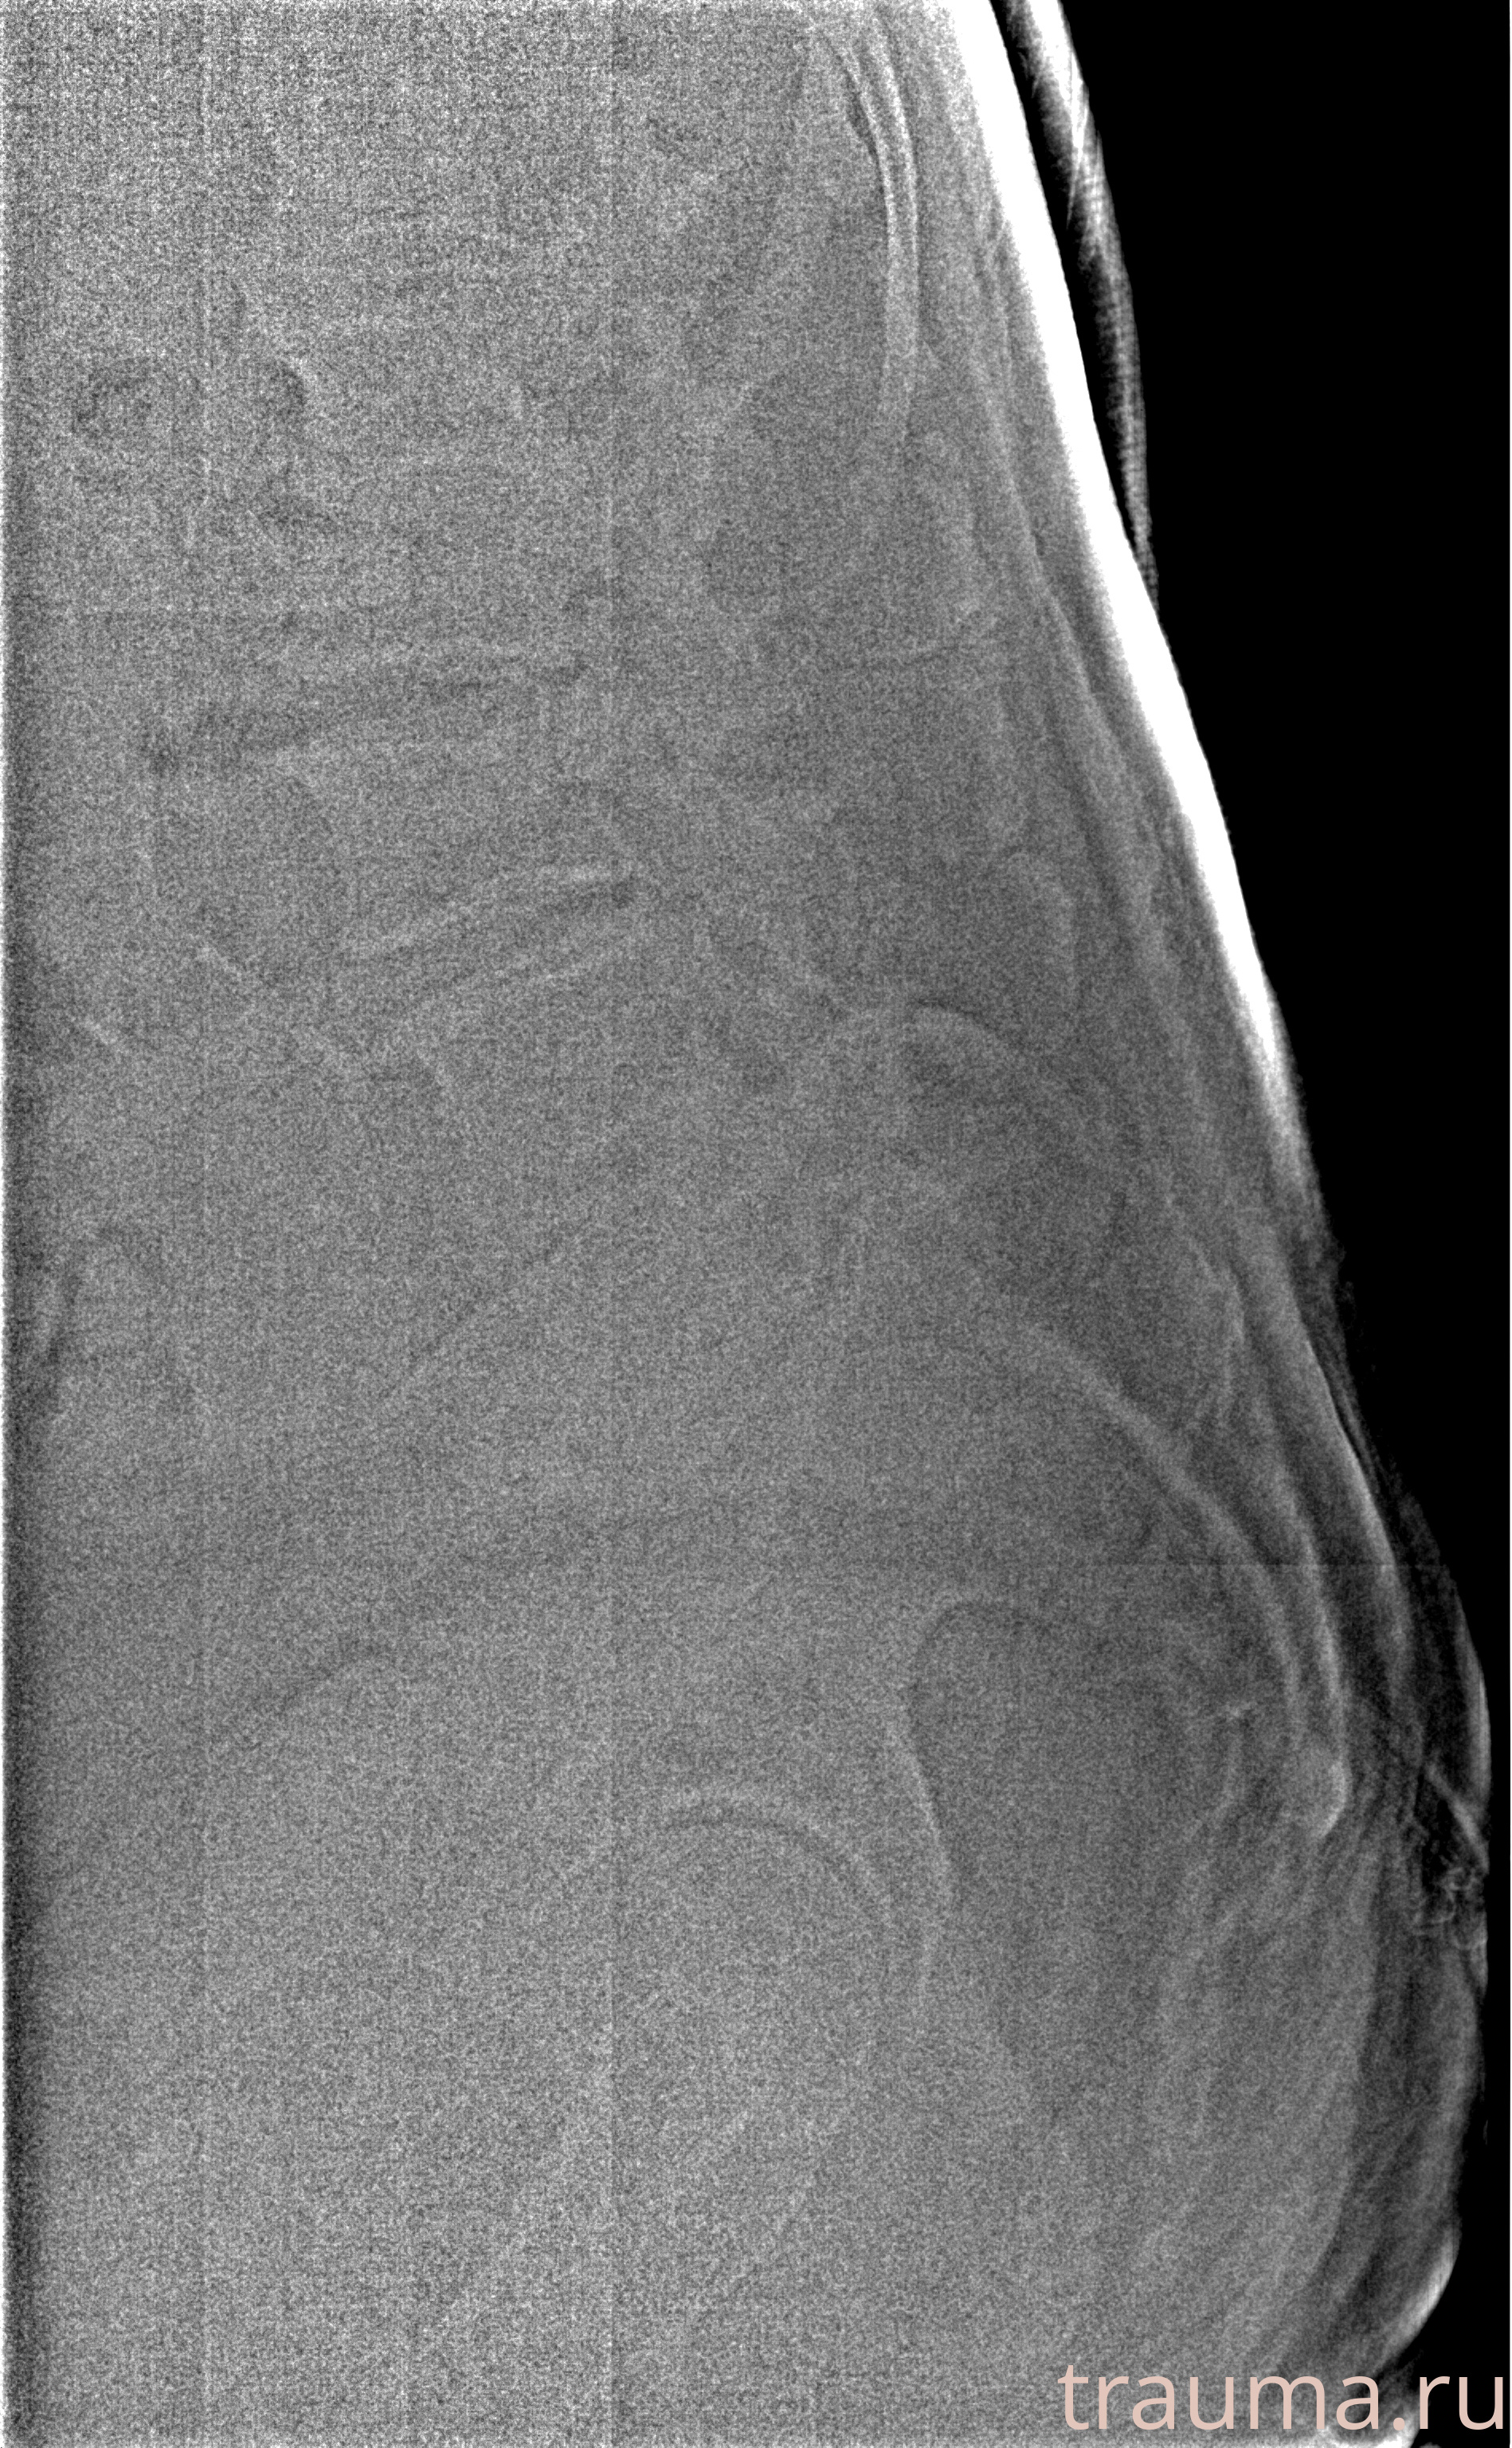

Рентген на дому: по вашему адресу приезжает врач-рентгенолог, травматолог-ортопед с мобильным рентгеновским аппаратом, проводит диагностику травмы или заболевания, делает необходимые рентгенограммы, дает рекомендации по дальнейшему лечению. Получить качественные снимки в домашних условиях возможно благодаря уникальной методике, разработанной МосРентген Центром для института  Склифосовского